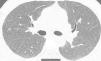

Presentamos el caso de un varón de 41 años, exfumador de 10 paquetes/año, pulidor de piedras preciosas en un taller de joyería desde hace 20 años, para lo cual utiliza material con una aleación de Be. Residente en entorno urbano, sin exposición a otras sustancias inhaladas. Fue remitido a neumología por referir disnea grado I (MRCm) en los últimos 4 meses, sin ningún síntoma respiratorio previo. El estudio de función pulmonar mostró FVC: 4.060ml (79%); FEV1: 3.330ml (81%); FEV1/FVC: 82%; RV: 2.430ml (116%); TLC: 6.570ml (89%); DLCO: 26,7ml/min/mmHg (79%) y KCO: 4,84ml/min/mmHg/l (91%). La tomografía computarizada de tórax permitió identificar un tenue patrón nodular de características centroacinares con densidad en vidrio deslustrado, de bordes mal definidos, bilateral y difuso, con un ligero predominio en lóbulos superiores. No se observó aumento de tamaño de ganglios hiliares ni mediastínicos (fig. 1). La biopsia transbronquial puso de manifiesto un tejido pulmonar con patrón preservado en zonas, con tabiques inter-alveolares finos, sin depósitos y que focalmente mostraba una infiltración inflamatoria con acúmulo de células epitelioides, bien delimitado, sin necrosis y con células multinucleadas, sin material extraño en su interior. El recuento celular del lavado broncoalveolar mostró el siguiente resultado: linfocitos 90%, neutrófilos 1%, macrófagos 8%, eosinófilos 0% y un cociente de linfocitos CD4/CD8 de 4. Se realizaron estudios microbiológicos completos del aspirado bronquial con resultados negativos.